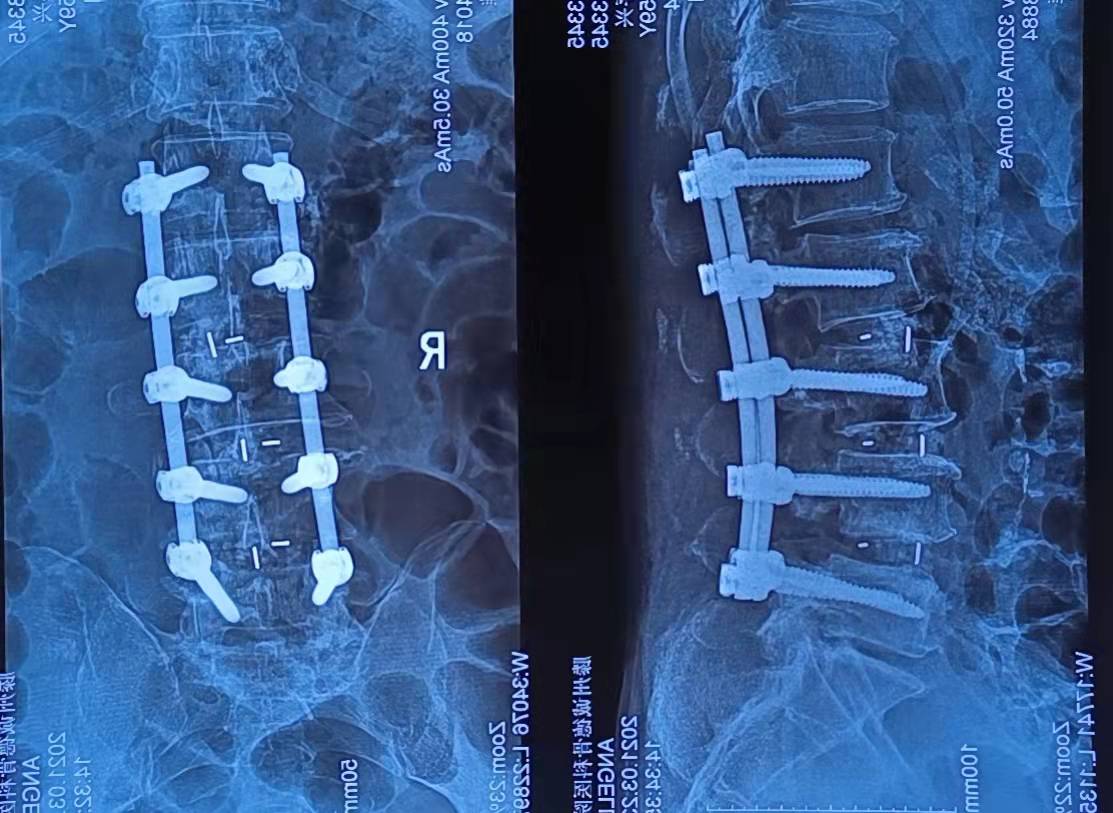

患者秦存興,男,59歲,腰痛多年勞累后加重,近一年來感腰痛伴雙側(cè)臀部、左大腿外側(cè)、小腿外側(cè)及右足麻木,行走50米后即感雙下肢疼痛劇烈,病痛的折磨給患者的生活帶來了很大的痛苦,讓他對未來失去了信心。來到誠德骨科醫(yī)院

經(jīng)查體、X片、CT及核磁共振檢查后確診為腰椎管狹窄癥,腰椎退變性滑脫,與患者充分溝通后決定行腰1-腰5減壓植骨內(nèi)固定術(shù)

術(shù)后患者癥狀立刻減輕,術(shù)后第三天下地行走,一月后復(fù)查患者步態(tài)如常,對治療結(jié)果非常滿意